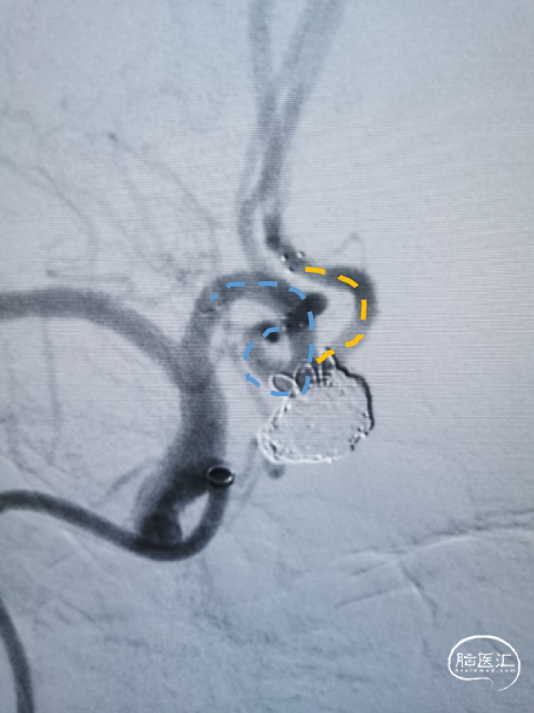

置入第一枚Atlas支架 3mm×15mm。

置入第二枚Atlas支架 4mm×21mm。

造影示“T”型支架左侧Atlas支架 3mm*15mm 、右侧 Atlas支架 4mm*21mm,动脉瘤致密栓塞,不显影。双侧A2段显影良好。

Atlas支架是激光雕刻开环支架,在不同直径动脉内释放时,短缩及延长非常微小。可以在释放之前,准确预估其完全放开后尾端的位置,支架组合能否形成完美“T”型,完全覆盖动脉瘤颈部非常重要。

在做“T”型支架时,两条支架释放的先后顺序各有千秋。本病例是先释放“竖”后“横”,这样可以是使“竖”支架尾端不受干扰地充分张开,“横”支架和前者充分贴合。